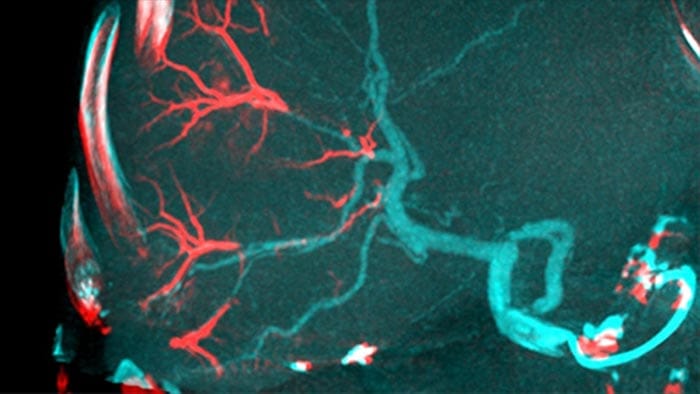

La adopción de técnicas de quimio/radioembolización como la QET y la Radioterapia interna selectiva (Selective Internal Radiotherapy, SIRT) impulsa la necesidad de estandarización y eficiencia. Caso tras caso, debe localizar de manera confiable y uniforme los tumores, identificar todos los vasos nutricios y planificar/llevar a cabo el enfoque intervencionista apropiado. Nuestra solución de Detección automática de alimentadores puede mejorar, de manera significativa, la detección de arterias nutricias en comparación con la TC de haz cónico sola. EmboGuide le ayuda a maximizar la eficacia de sus procedimientos de QET, ya que potencialmente mejora su sensibilidad, reduce los falsos positivos y maximiza la concordancia entre lectores.1

La capacidad de detectar y de distinguir nódulos hepáticos e identificar los vasos minúsculos del alimentador es fundamental para determinar el tratamiento apropiado. Navegar a la región de interés y llegar a todos los alimentadores, sin dejar de ser selectivo con la lesión, aumenta la oportunidad de éxito. La confirmación del punto final del tratamiento y el éxito de este mientras el paciente está todavía en la mesa incrementa la confianza en los resultados clínicos.